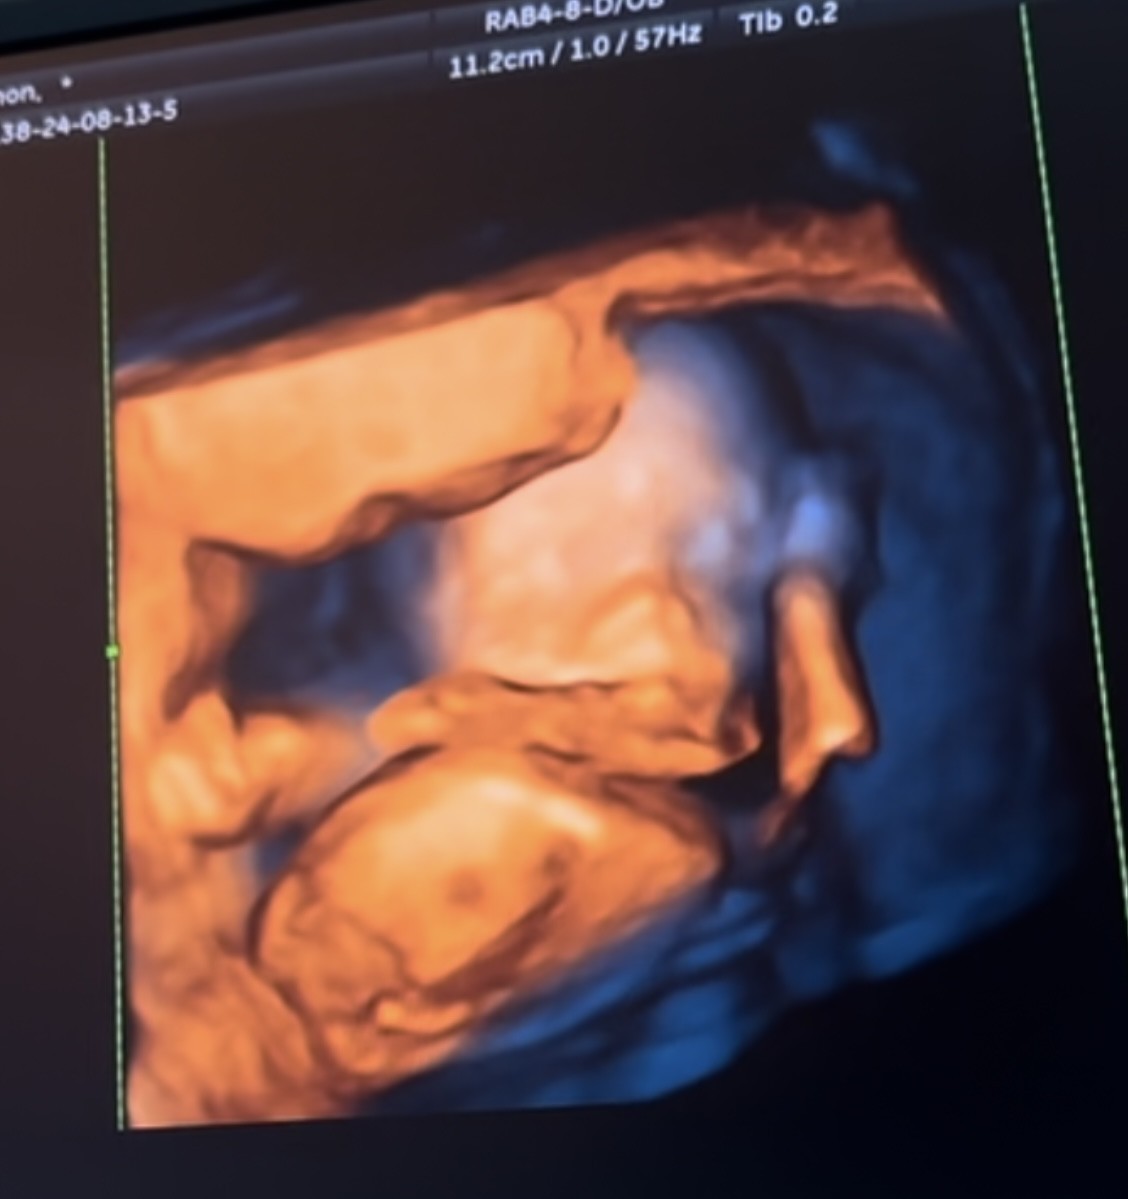

Dziewczynka czy chlopak? Usg

Prosze jak uwazacie oczywiscie plci nie chcialam znac a teraz mnie meczy to bo nie wiem jak do niej/niego śpiewać😀

• IMG_1086.jpeg

IMG_1086.jpeg

103,8 KB · Wyświetleń: 107